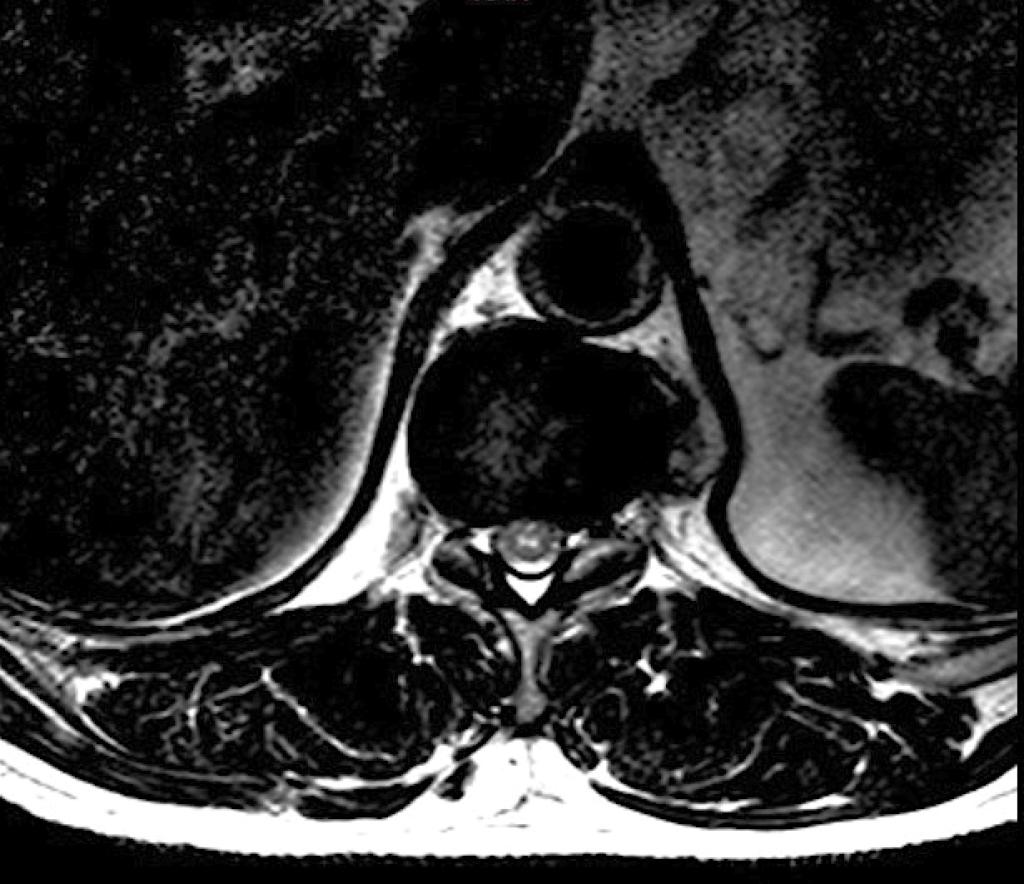

Een 61-jarige man met meerdere cardiovasculaire risicofactoren komt naar de SEH wegens acute rugpijn, gevolgd door een in uren progressief krachtverlies van beide benen, en darm- en blaasledigingsstoornissen. Bij onderzoek is de vitale sensibiliteit afwezig vanaf niveau T11, maar zijn de propriocepsis en vibratiezin gespaard. MRI van de thoracolumbale wervelkolom verricht na 24 h laat een langgerekte hyperintense T2-afwijking zien aan de voorzijde van het myelum op niveau T10-12. Een axiale opname toont dit beeld.